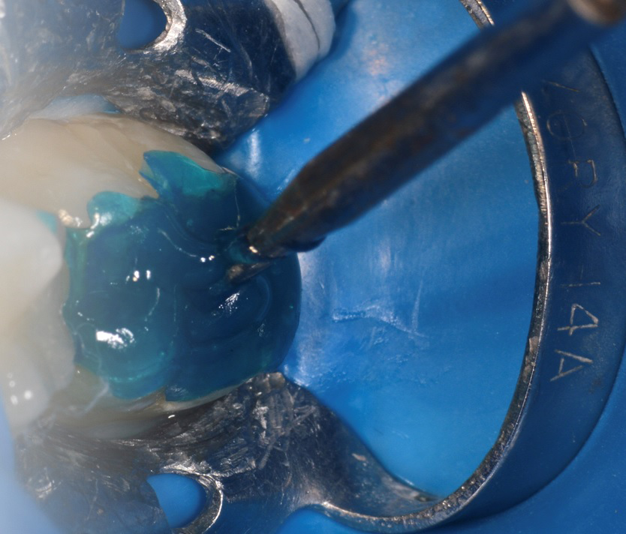

To create the pattern – i.e., the “stamp” – place soap or other separating medium on the occlusal surface of the tooth and flow a low viscosity resin or hard setting liquid dam material onto the surface (Fig. 2). Place a bur shaft (or microbrush) into the resin, and light cure. The bur shaft will act as the handle for the stamp (Fig. 3). Prepare the cavity in the usual manner (Fig. 4).

Fig. 3: The cured stamp with bur attached for a handle. Fig. 4: The cavity after removal of decay. Fig. 5: The mesial surface restored with ACTIVA BioACTIVE-RESTORATICE and light cured.